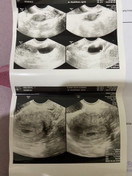

ini hasil USG q wktu 9w sekarang Alhamdulillah udah 15w

Aku waktu itu pas hamil 6 week baru keliatan kantung nya aja bun itu jg pakai USG transvaginal

kmren sya udh kliatan bun pas usg 6 w, tpi ada jga yg blom kliatan mnkn beda2 y tiap org

alhamdulillah bun 6w 1 hri sdh kelihatan kantungnya via usg transvaginal

Kalau saya usia 7 minggu baru keliatan janin bun alhamdulillah udh ada detak jantungnya

aku 6w udah keliatan bun, tp pake transvaginal udah terdengar detak jantung juga hihi